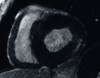

Kardiologischen Untersuchungsverfahren

Zu den kardiologischen Untersuchungsverfahren zählen bildgebende Verfahren wie die Elektrokardiographie (EKG), die Echokardiographie (Echo) und die Magnetresonanztomographie (Kardio-MRT mit Late Enhancement Imaging).

Typisch bei Morbus Fabry ist eine linksventrikuläre Hypertrophie zumeist ohne Hypertonie, ein prominenter Papillarmuskel und eine gestörte Klappenfunktion. Im EKG zeigt sich oft eine verkürzte PQ-Zeit und eine T-Wellen-Inversion.8

Bild einer MRT Untersuchung

Bild eines MRT

Typische Echokardiographie eines Morbus Fabry-Patienten (links), Magnetresonanztomographie mit Late-Enhancement-Technik zur Darstellung einer myokardialen „Replacement-Fibrose“ (rechts)

Mit freundlicher Genehmigung von Prof. Dr. Frank Weidemann, Recklinghausen